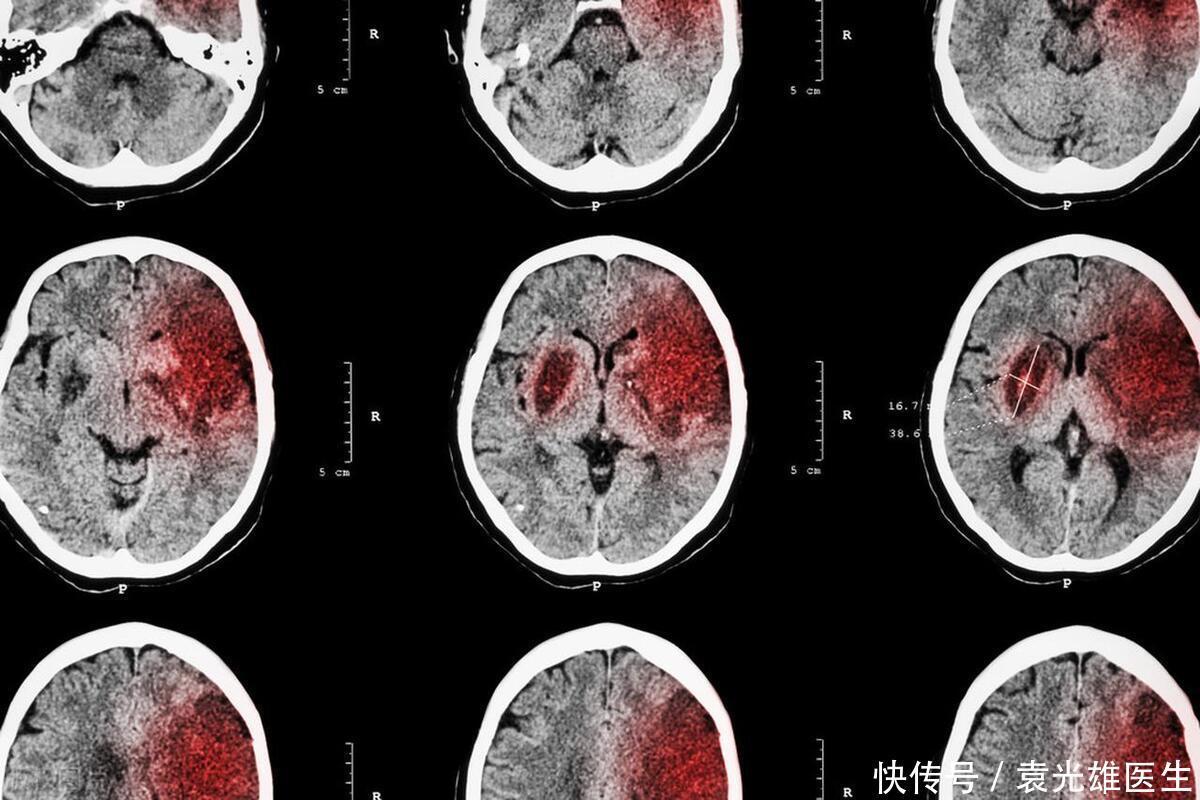

脑梗,如同脑血管中悄然降临的“堵塞卫士”,无情地截断了血液通往大脑的畅通之路,使得大脑的部分区域陷入缺血缺氧的困境,严重威胁着患者的生命与健康。若未能及时采取应对措施,脑梗这一疾病就如同潜伏的威胁,极有可能引发不可逆转的严重后果,其潜在的破坏力足以威胁到患者的生命安全,不容忽视。

在那一刻,他深刻意识到了问题的紧迫性,不敢有丝毫的耽搁,立刻前往医院,进行了详尽的脑部CT检查,以了解具体的健康状况。经过精密的医学检查,结果显示他的脑血管已经遭受了部分阻塞,这一发现让医生们确诊他罹患了脑梗,这一严重的健康状况无疑给他的生活带来了极大的挑战和不安。